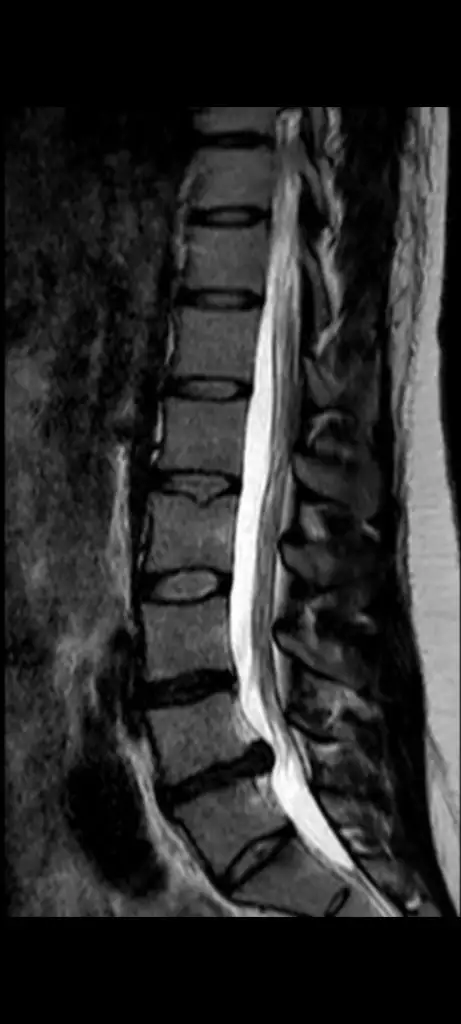

30 yasindayim 75 kiloyum l4 l5 te fitik ve baya buyuk patlamak uzere denildi. Size foto yolluyorum ayni yerde miydi sizinde? Bacaktan neden ameliyat oldunuz orayi anlamadim?Dediğim gibi kapalı açık mı ameliyat olduğumu bilmiyorum kesim 3 cmdi. Hayat kalitem sıfırdı yürüyerek Bi yere gidemiyordum, ev işleri ağlayarak yapıyordum mecburiyetten. Dezavantajları hep dikkat etmek zorundasın ağır kaldırırken eğilip kalkarken yatıp kalkarken. Mesela hala klozet kullanıyorum diğeri benim için zor geliyor. Ameliyattan sonra belli bir süre ağrılarım oldu mesela Benim sol ayağım parmaklarım aşırı derecede uyuşuktu onlar biraz devam etti 2 ay falan olduğunda komple bütün şikayetlerim bitmişti. Ameliyat olduğuma hiç pişman olmadım. 10 günün sonunda Bi yemeğini yapacak kadar iyi oluyorsun hatta evi bile süpürür sün kendini hırpalamadan ama en az 1 ay dinlenmende fayda var yanında biri olması iyi olur. Sol bacaktan ameliyat oldum ben. Solla bir sıkıntım yok bazen benim sağ bacağım ağrıyor ama doktor fıtık yok dedi. Bilmiyorum neyden ağrıyor. Kaç yaşındasın. Kaç kilosun ve fıtığın L kaçta bilyor musun

Evet aynı yerde büyüklükleri de hemen hemen aynı gibi. Bacaktan oldum derken fıtık sol bacağıma vuruyordu. Soldaki sinire bası mevcuttu. Zayıflamının fıtığa iyi geldiğini söylüyorlar ama dediğim gibi ben ameliyat olmanızı öneririm eminim Ankarada iyi doktorlar vardır30 yasindayim 75 kiloyum l4 l5 te fitik ve baya buyuk patlamak uzere denildi. Size foto yolluyorum ayni yerde miydi sizinde? Bacaktan neden ameliyat oldunuz orayi anlamadim?